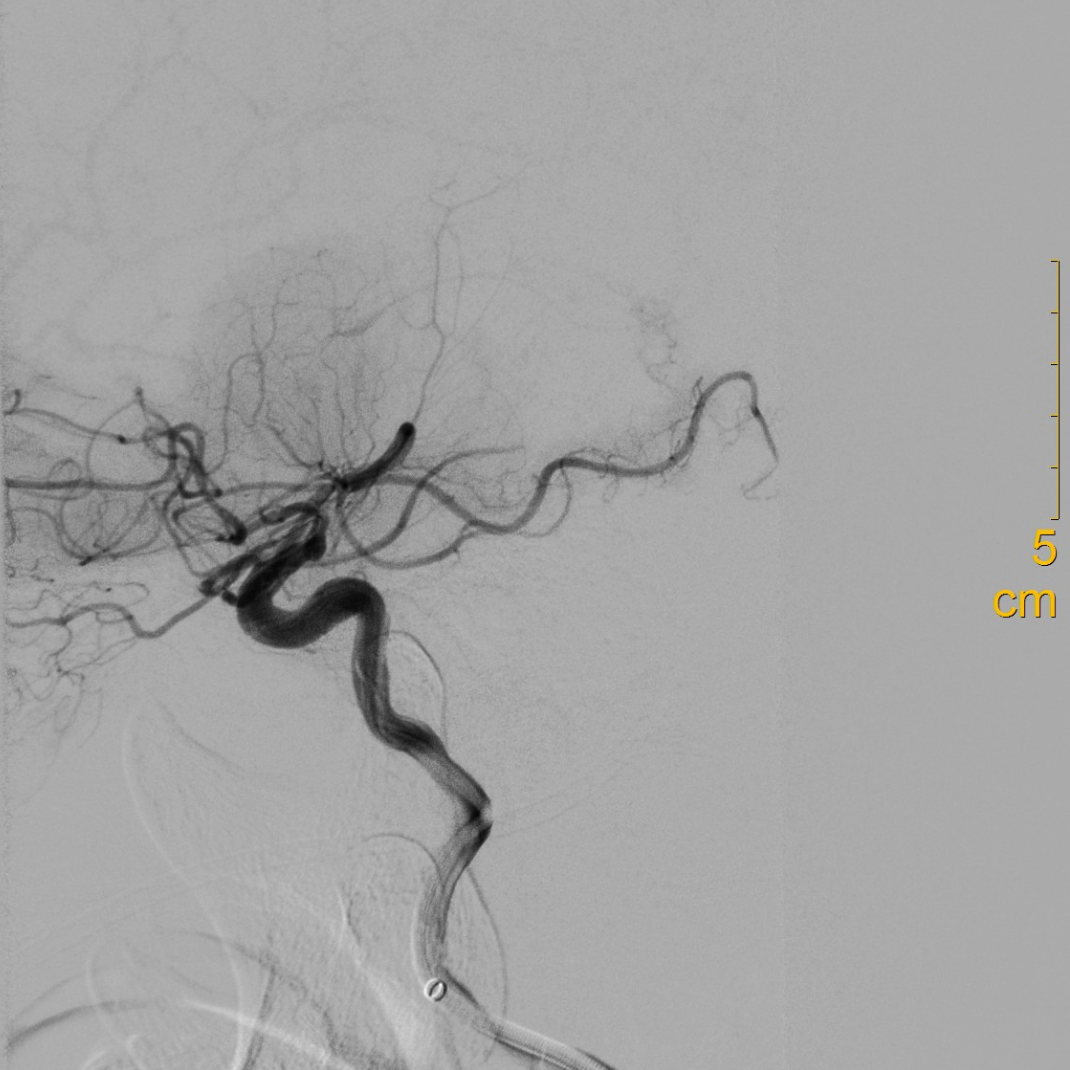

造影可见闭塞残端细小,结合多时相CT,考虑倾向于狭窄性病变。

什么叫桡鞘【例久弥新】寻道于桡——瑞康通5.5F IntroSky X导管鞘经桡动脉行右侧大脑中动脉取栓一例_https://www.jmylbn.com_新闻资讯_第14张